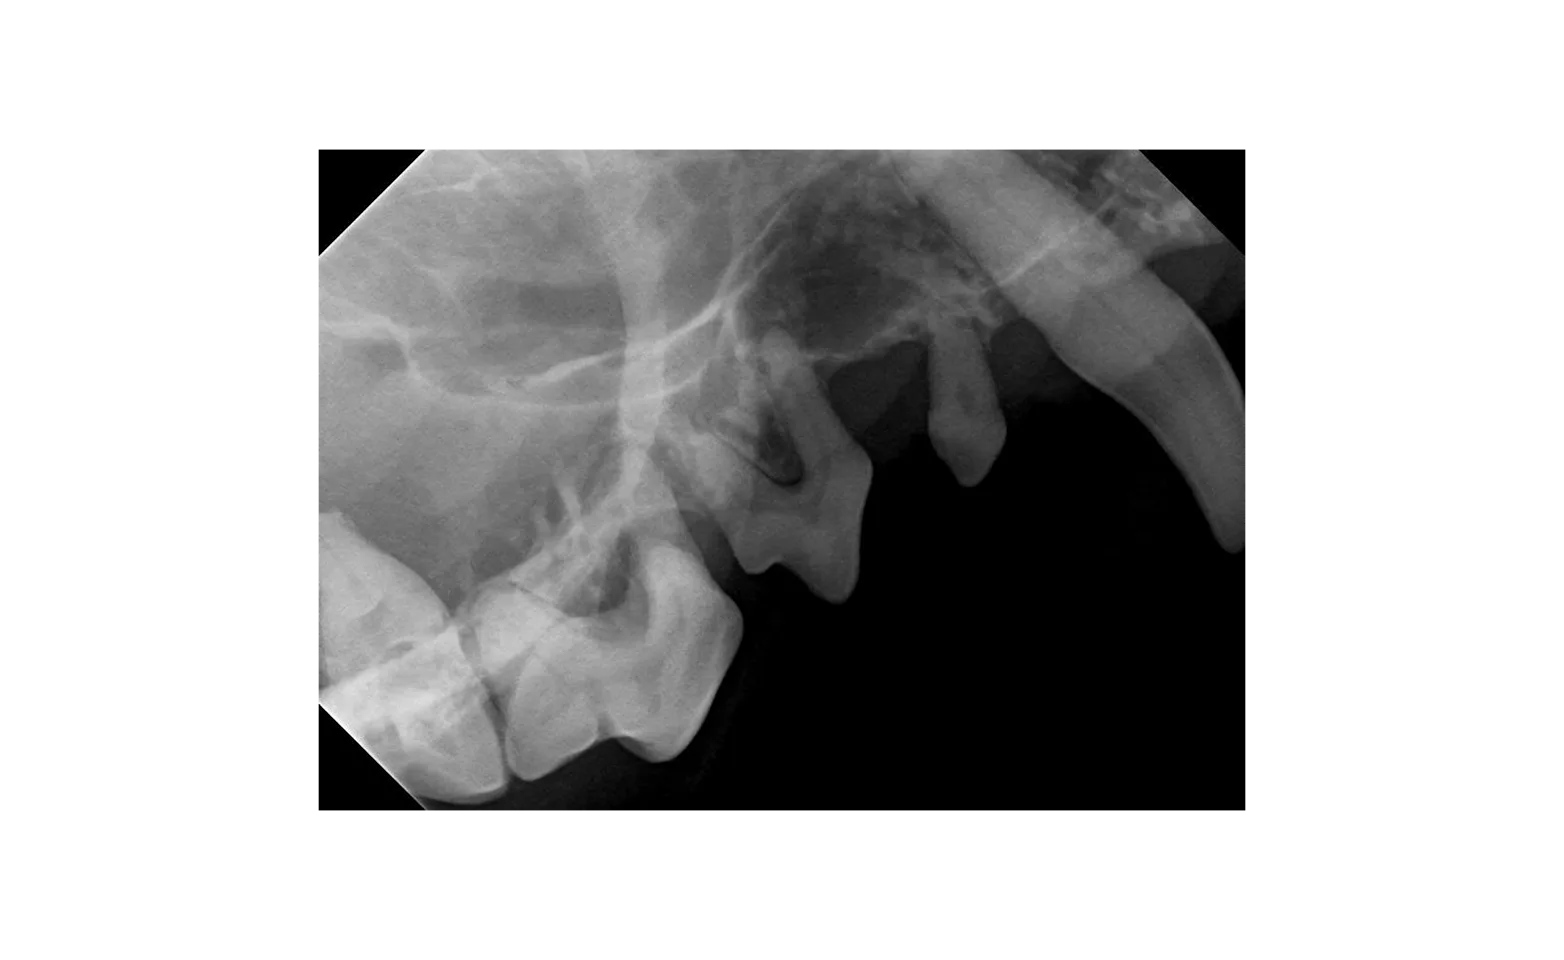

A large portion of your pet’s teeth reside underneath the gum-line. So, most of the bacteria build-up and excess food debris that causes significant inflammation and deterioration of the gums are almost impossible to see. Our digital radiographs allow us to see the condition of the teeth below the gum-line, and we can ensure that your pet’s teeth are truly cleaned with our ultrasonic scaler. Our recommended dental services ensure that your pet receives the highest quality dental care possible.